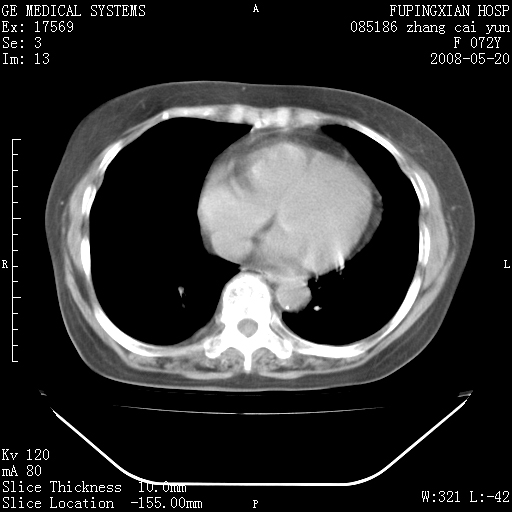

标题: CT13542:发热,咳嗽数日,经抗菌素治疗好转,请大家看排除 [打印本页]

标题: CT13542:发热,咳嗽数日,经抗菌素治疗好转,请大家看排除

上叶支气管略变窄并通畅,内壁光滑。考虑:单纯阻塞性肺炎!

右上叶支气管走行自然,未见明显管壁增厚等征像,另左主支气管起始部可见异常腔道向左侧延展左肺动脉干后方,与左下叶支气管相通,为左下叶支气管变异?

有节段性阻塞性肺炎与不张,近段支气管狭窄,周围散在肿大淋巴结影,以周围型肺癌可能性大,建议纤支镜检查。

右肺上叶实变影,内见支气管充气征,右上叶支气管通畅,肺门区未见软组织密度影,抗炎治疗有效,考虑炎症,建议继续抗炎治疗复查。

右上肺实变,间内有支气管充气征,考虑炎症,建议抗炎后复查